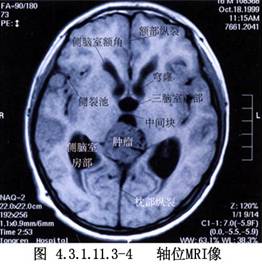

1966年Poppen最先在临床上采用枕部经小脑幕入路切除松果体区肿瘤,Jemieson又在1971年加以改进。经此入路不损伤重要组织,术野显露宽敞,不仅可进入第三脑室,还可达到小脑上蚓部、第四脑室上部及胼胝体后部,提高了肿瘤的全切率,手术的死亡率及致残率也较低。国内王翚、罗世琪分别于1983年报道了此入路的手术经验,1988罗士琪又报道了64例经验,死亡率降至5%以下,王翚对此手术曾加以改进,即根据需要可切断小脑前中央静脉,并在切开小脑幕后,进而切开小脑镰,使术野宽敞,便于操作。目前此入路应用比较广泛。(图4.3.1.11.3-1~4.3.1.11.3-6)

此部蛛网膜常常增厚呈乳白色,在分离时应小心,注意保护大脑大静脉和注入该静脉的基底静脉、枕内静脉、两侧大脑内静脉及小脑前中央静脉,肿瘤即在大脑大静脉的前方(图4.3.1.11.3-11)。